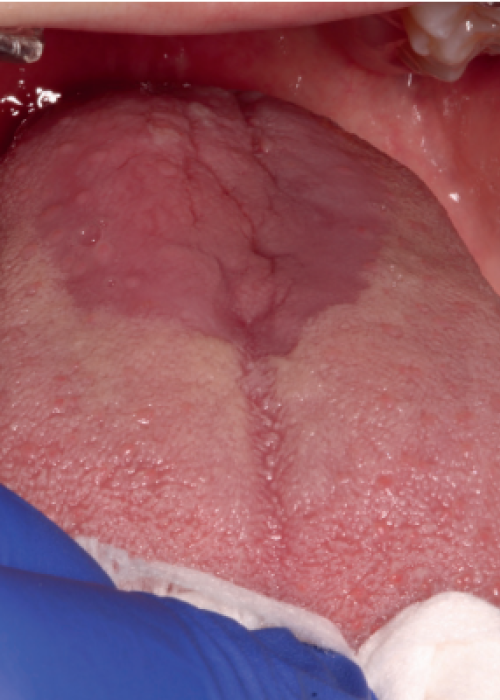

Assessment of the different therapy options in the clinical management of Burning Mouth Syndrome (BMS)